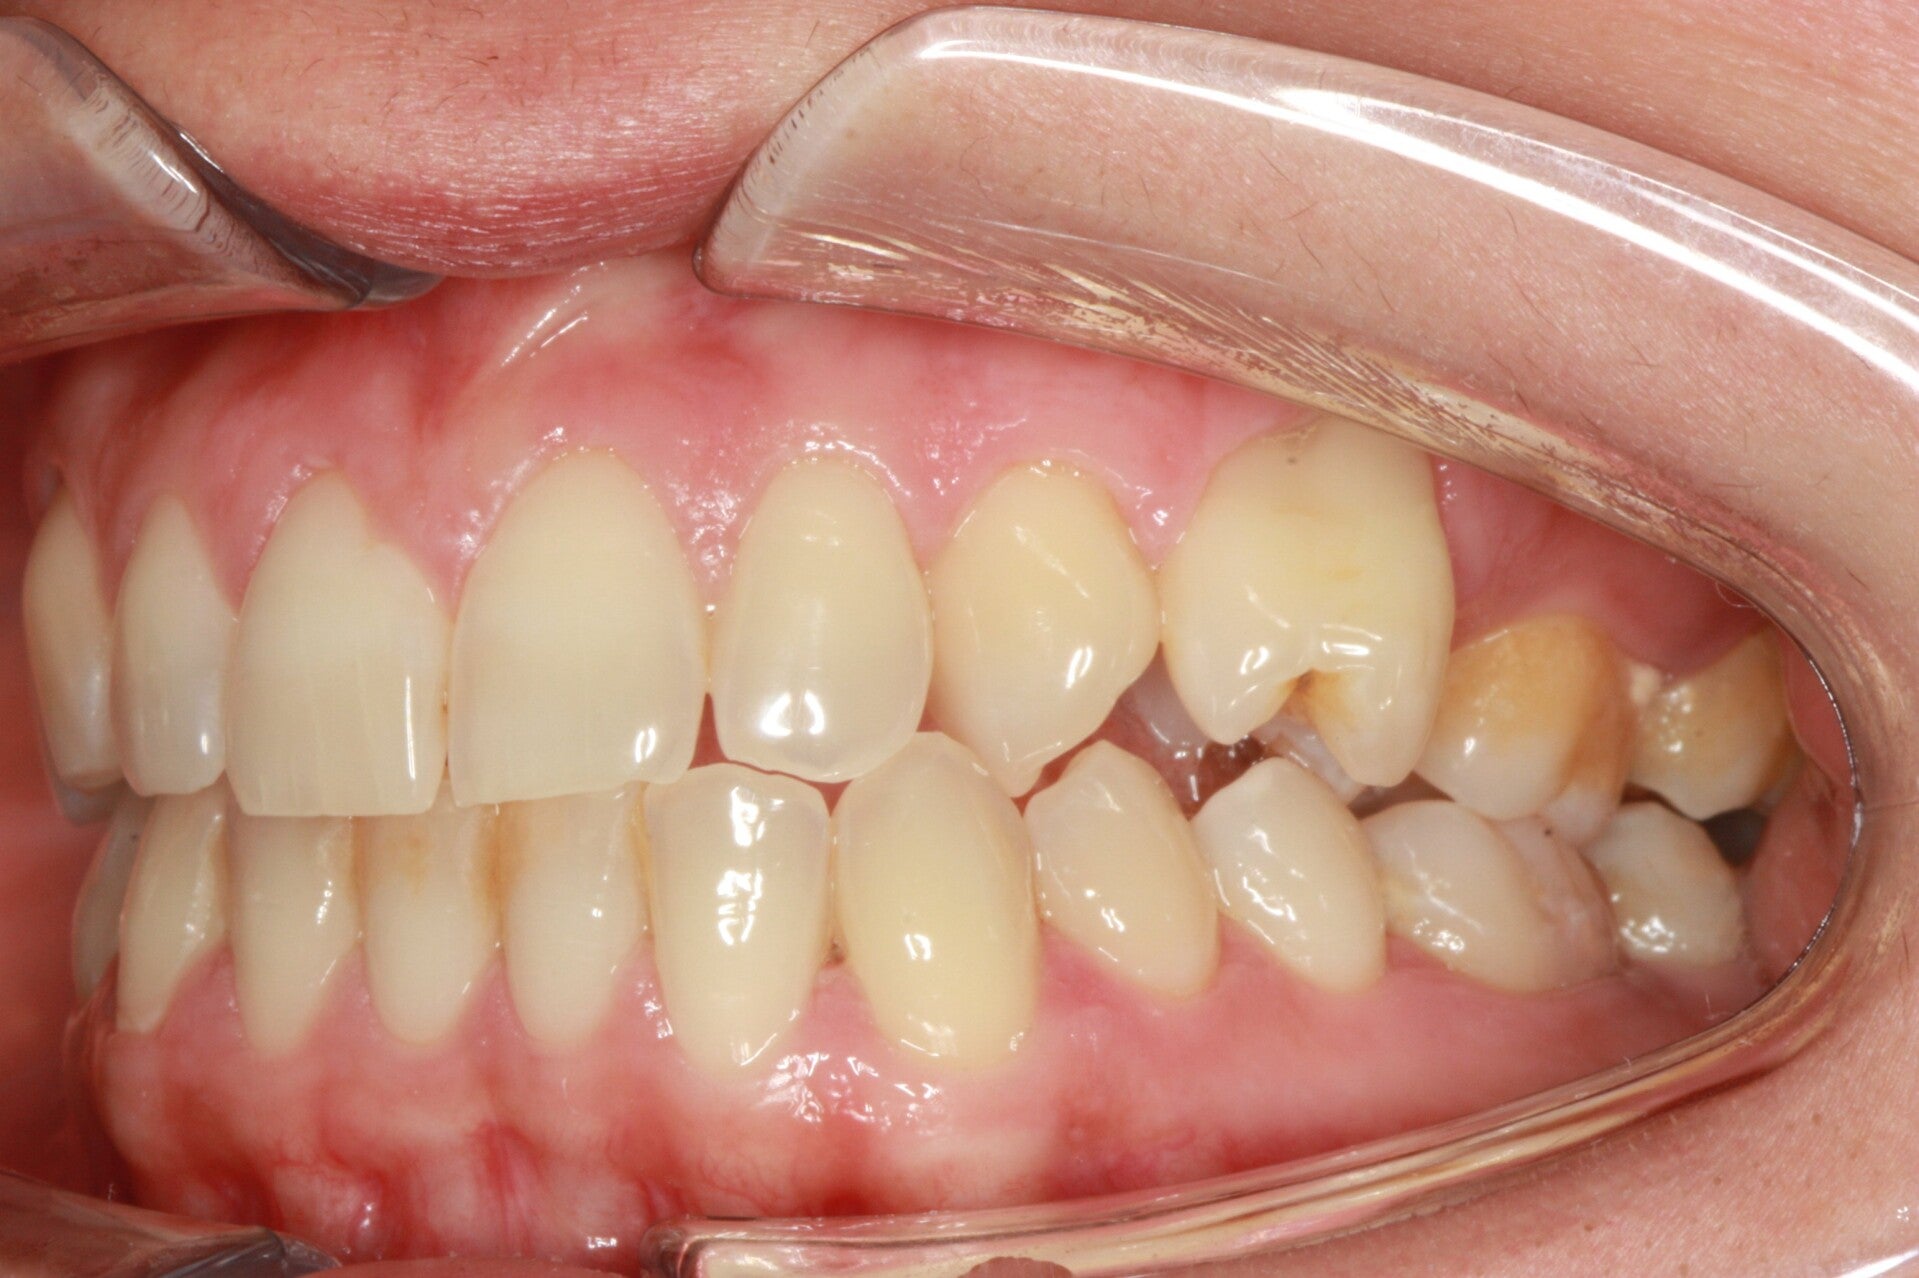

FOTO FINALI DOPO 24 MESI CIRCA DI TERAPA ORTODONTICA FISSA

PRIMA CLASSE CON AFFOLLAMENTO GRAVE SUPERIORE A SINISTRA CON PERDITA PRECOCE DEL SECONDO MOLARE INFERIORE SINISTRO

Abbiamo appena portato a termine questo caso che presentava in arcata superiore il primo premolare di sinistra completamente fuori arcata sovrapposto al secondo premolare ed il canino ruotato.

in arcata inferiore invece abbiamo estratto il secondo molare di sinistra perso per carie deostruente e mesializzato il terzo molare in modo da chiudere lo spazio e non ricorrere all'inserimento di protesi implantare.